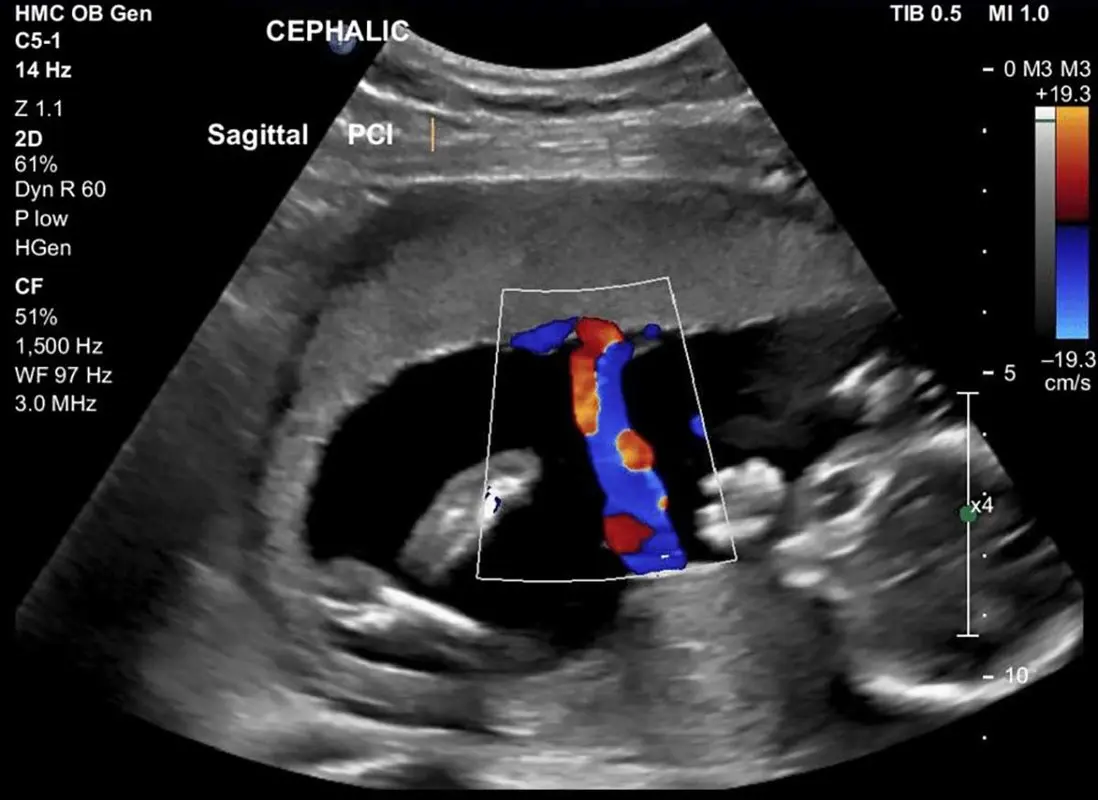

سونوگرافی کالر داپلر به منزله انقلابی در تکنولوژی سونوگرافی مطرح است. سونوگرافی کالر داپلر این امکان را فراهم میسازد که سرعت و جهت جریان خون در عروق بررسی شود.

یکی از مهمترین کاربردهای سونوگرافی بررسی حرکت خون در شریان ها و رگ ها ست. سونوگرافی دو بعدی و سه بعدی، ساختار داخلی اندام ها و بافت ها را نشان می دهند و سونوگرافی کالر داپلر جریان و فشار خون در رگ ها را بررسی می کند.

در این نوع از سونوگرافی امواج فراصوت به بدن ارسال می شوند و با سلول ها و گلبول های خون برخورد کرده، طول موج آنها تغییر می کند. بعد از برگشتن به دستگاه تغییرات به وجود آمده در طول موج ها تصاویر سونوگرافی کالر داپلر را می سازند. اطلاعات به دست آمده از این ارسال و برگشت امواج نشان می دهد که جریان خون در رگ ها و شریان های سونوگرافی شده با چه سرعت و در چه جهت حرکت می کند، آیا انسداد یا افت سرعت حرکت در شریان ها وجود دارد یا خیر.

که از طیف رنگ های مختلف برای نمایش جریان خون و ساختار بافت ها و اندام ها استفاده می کند. این نوع از سونوگرافی سرعت جریان خون در رگ ها و جهت حرکت آن را با کیفیت بیشتری نشان می دهد.